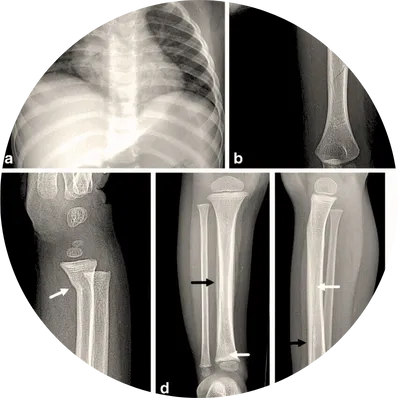

Implant removal surgery is a procedure to take out orthopedic implants (such as plates, screws, rods, or pins) that were used to stabilize bones after a fracture or corrective surgery. While implants are usually designed to stay permanently, sometimes they need to be removed due to complications or discomfort.

The procedure is performed under regional or general anesthesia. The surgeon reopens the previous incision to access the implant and carefully removes plates, screws, rods, or nails without disturbing the healed bone. Specialized tools are used to gently disengage the hardware while protecting surrounding muscles and nerves.

If infection or tissue irritation is present, the surgeon cleans the area, removes infected tissue, and washes the surgical site thoroughly to promote healing and prevent recurrence.

In cases where bone strength is inadequate or removal may compromise stability, temporary support such as splints, braces, or casts may be provided until full recovery.